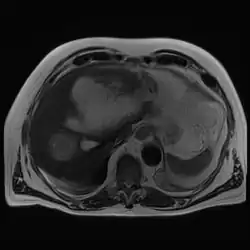

Amoebic liver abscess

A amoebic liver abscess is a type of liver abscess caused by amebiasis.[1] It is the involvement of liver tissue by trophozoites of the organism Entamoeba histolytica and of its abscess due to necrosis.